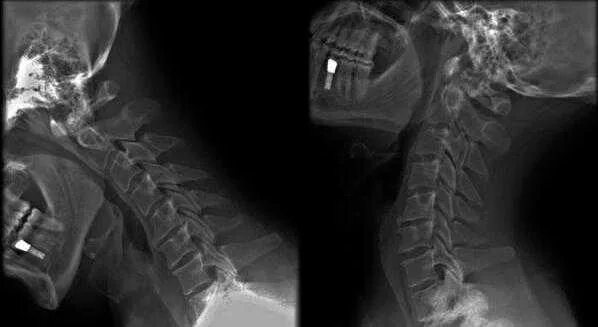

Что значит нарушение статики позвоночника